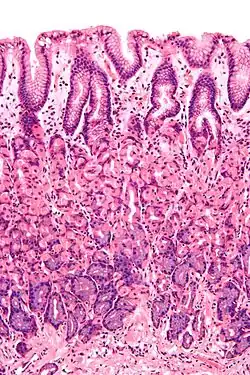

Foveolární buňky jsou mukózní buňky cylindrického tvaru, které v jedné vrstvě vystýlají povrch žaludku a žaludeční jamky. Někdy se mezi ně řadí i mucinózní buňky krčků, které se nachází mezi parietálními buňkami ve vývodech žaludečních žlázek na povrch žaludku. [1]

Mukózní buňky tvoří jednovrstvý epitel na vnitřním povrchu žaludku a v žaludečních jamkách. Tyto jamky vznikají zanořováním epiteliálních buněk do lamina propria mucosae, vrstvy řídkého kolagenního vaziva nacházející se pod epitelem, a ústí do nich žaludeční žlázky. [1]

Epiteliální buňky mají cylindrický tvar. Jsou vysoké 20-40 µm. Jádro, kulové či oválné, je uložené u báze buněk, kde se také nachází granulární endoplazmatické retikulum a nad ním Golgiho aparát. V apikální části buněk se vyskytují četná světlá hlenová granula.[5]

Mucinózní buňky krčků, které lemují žaludeční žlázky, jsou jim podobné. Osahují typická kulatá jádra a apikálně uložená sekreční granula, ale jsou nižší a mohou mít nepravidelný tvar.[6][7]